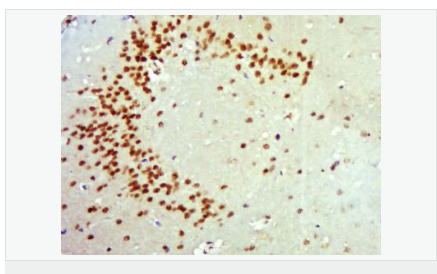

| 產(chǎn)品應(yīng)用 | WB=1:500-2000 ELISA=1:5000-10000 IHC-P=1:100-500 IHC-F=1:100-500 ICC=1:100-500 IF=1:100-500 (石蠟切片需做抗原修復(fù)) not yet tested in other applications. optimal dilutions/concentrations should be determined by the end user. |

| 細胞定位 | 細胞核 分泌型蛋白 |